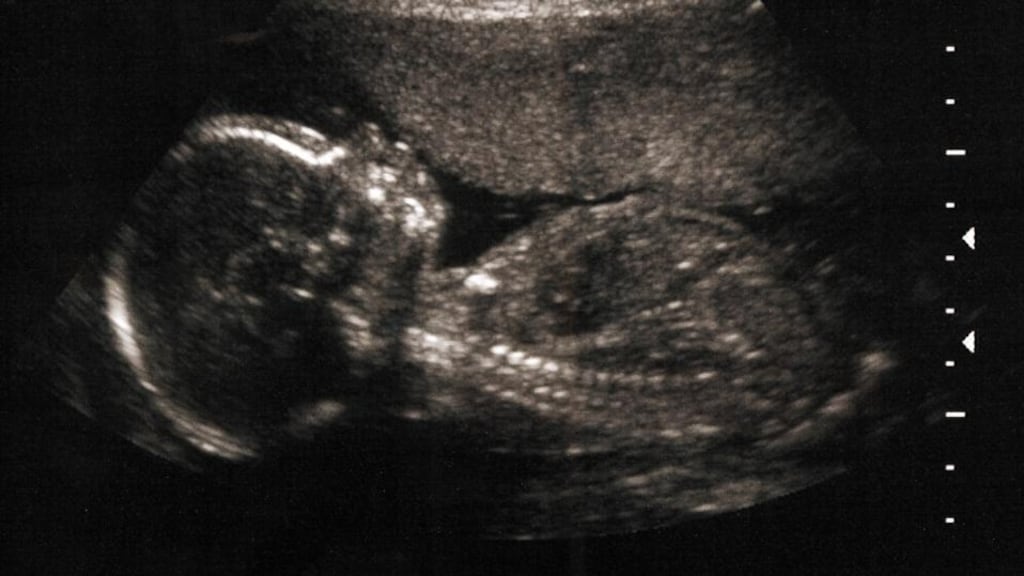

Thompson explained: “Foeticide is performed when one is terminating a pregnancy after 22 weeks of gestation. We tend to do this under ultrasound control and gain access to the foetal circulation, sometimes through the heart. It is important that one then paralyses the foetus by administering a drug much as one would with a general anaesthetic, followed by an injection of either a local anaesthetic or potassium, which stops the heart.